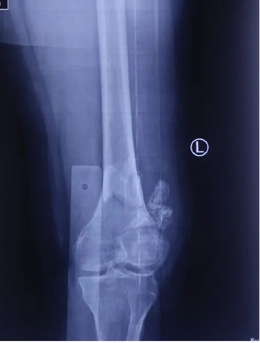

吴新宝团队对患者检查后发现患者系典型老年骨质疏松性骨折,膝关节周围有明显老年退行性改变;股骨远端大量骨性增生导致骨折部位解剖形态与青壮年成人有明显差异,股骨前弓明显增大;同时老年患者骨愈合能力下降,容易发生骨折不愈合,内固定物失效等并发症。如何更好地解决老年骨质疏松性骨折这一临床问题,降低手术并发症是骨科医生面临的一个临床挑战。

其次,定制化接骨板的形态设计是以患者的个人CT数据为参考,完全根据患者个人的解剖形态而打印制造,与患者股骨远端解剖形态完全一致,便于手术中骨折的复位固定; 另外接骨板钉孔设计参考了骨折端的解剖形态和生物力学特点,骨折端的接骨板形态得到了强化设计,并同时计算了手术中所需螺钉的长度,实现了精准化置钉功能,简化了手术操作。

吴新宝团队术前详细规划,反复推演手术流程。2021年9月27日,在短短不到1小时的时间内,手术团队按照手术设计顺利完成了骨折的复位固定。术中影像显示,骨折解剖复位,定制钢板位置得当,螺钉位置理想,完美实现了术前规划的手术目标。